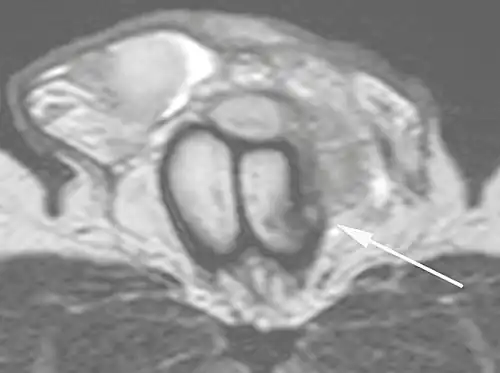

Ultrasound examination is able to depict the tunica albuginea tear in the majority of cases (as a hypoechoic discontinuity in the normally echogenic tunica). In a study on 25 patients, Zare Mehrjardi et al. concluded that ultrasound is unable to find the tear just when it is located at the penile base. In their study magnetic resonance imaging (MRI) accurately diagnosed all of the tears (as a discontinuity in the normally low signal tunica on both T1- and T2-weighted sequences). They concluded that ultrasound should be considered as the initial imaging method, and MRI can be helpful in cases that ultrasound does not depict any tear but clinical suspicions for fracture are still high. In the same study, authors investigated accuracy of ultrasound and MRI for determining the tear location (mapping of fracture) in order to perform a tailored surgical repair. MRI was more accurate than ultrasound for this purpose, but ultrasound mapping was well correlated with surgical results in cases where the tear was clearly visualized on ultrasound exam.[10] The advantage of ultrasound in the diagnosis of penile fracture is unrivaled when its noninvasive, cost-effective, and nonionising nature are considered.[11]

B: Axial T2-weighted turbo spin-echo magnetic resonance imaging scan showing left-sided discontinuity of the tunica albuginea (arrow), secondary to fracture.[2]